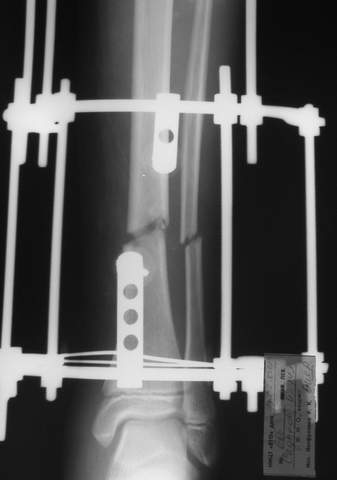

Под рукой прилагаемый пример. Как видите, "стриптиз-аппарат" (шутка проф. З.К.Башурова): 3 кольца-2 кольца-2 полукольца. В случае, который представил Евгений, характер повреждения позволил бы сразу использовать аппарат на основе 2 колец; в крайнем случае прокс. опора м.б. демонтирована сразу после репозиции.

3a

3b

3c

В аттачте № 3 - один из примеров полукольцевого аппарат...

Это уже я баловался.

Итог? Работы больше (по времени и

интраоп "подгонке"), срастается также, а особого преимущества по сравнению с

"чиста" кольцевым (вес, удобство ношения и пр.) - я, по крайней мере,

не нашел.

Теперь не балуюсь.